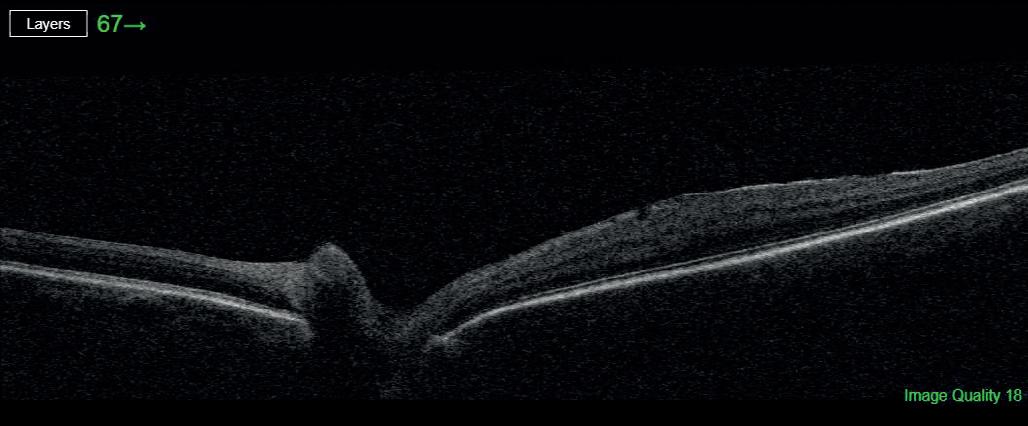

Most astronauts experience changes to the structures of their eyes and brains while in space flight, including swelling at the back of the eye called optic disc oedema (ODE).

The size of effects and time of onset of ODE varies widely between individuals. While changes tend to be reversed when crew members return to Earth, there are concerns that extended missions, such as those being proposed to the moon and Mars, could increase the risk of permanent vision problems.

US-based researchers analysed data on 31 astronauts who spent six to 12 months on the International Space Station. They found that 23 of the astronauts developed signs of ODE. Average total retinal thickness increased from a pre-flight average of 392.0μm to 430.2μm after around 150 days in space.

It has previously been suggested that those with a small or non-existent optic cup, an area at the centre of the optic disc, are more at risk of developing ODE during spaceflight (Stenger et al, 2019).

In the new study, published in JAMA Ophthalmology, the researchers found that astronauts with small, shallow and narrow optic cups pre-flight experienced larger increases in retinal thickness while in space. No other pre-flight ocular measures were associated with ODE.

Only six women took part in the study, so it is limited in its applicability to female astronauts. It was also not possible for in-flight measurements to be collected after the same number of days, and the length of time since participants had taken part in previous space missions was not considered.

The findings, nonetheless, support the idea that astronauts with smaller optic cups may benefit from increased monitoring and use of countermeasures. bit.ly/3igZr70